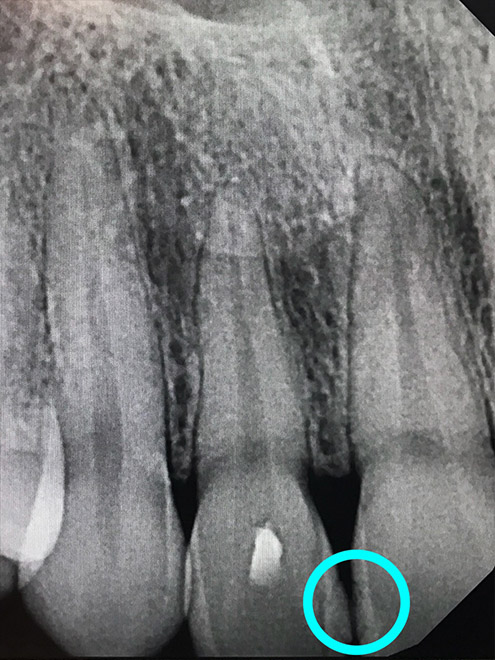

Ozone Treatment :

Bone healing with ozone treatment and SRP

Reverse Gum Disease: Bone Healing

Reverse Tooth Decay: After 10 sessions of ozone gas infiltration treatment, the tooth regains its shape.